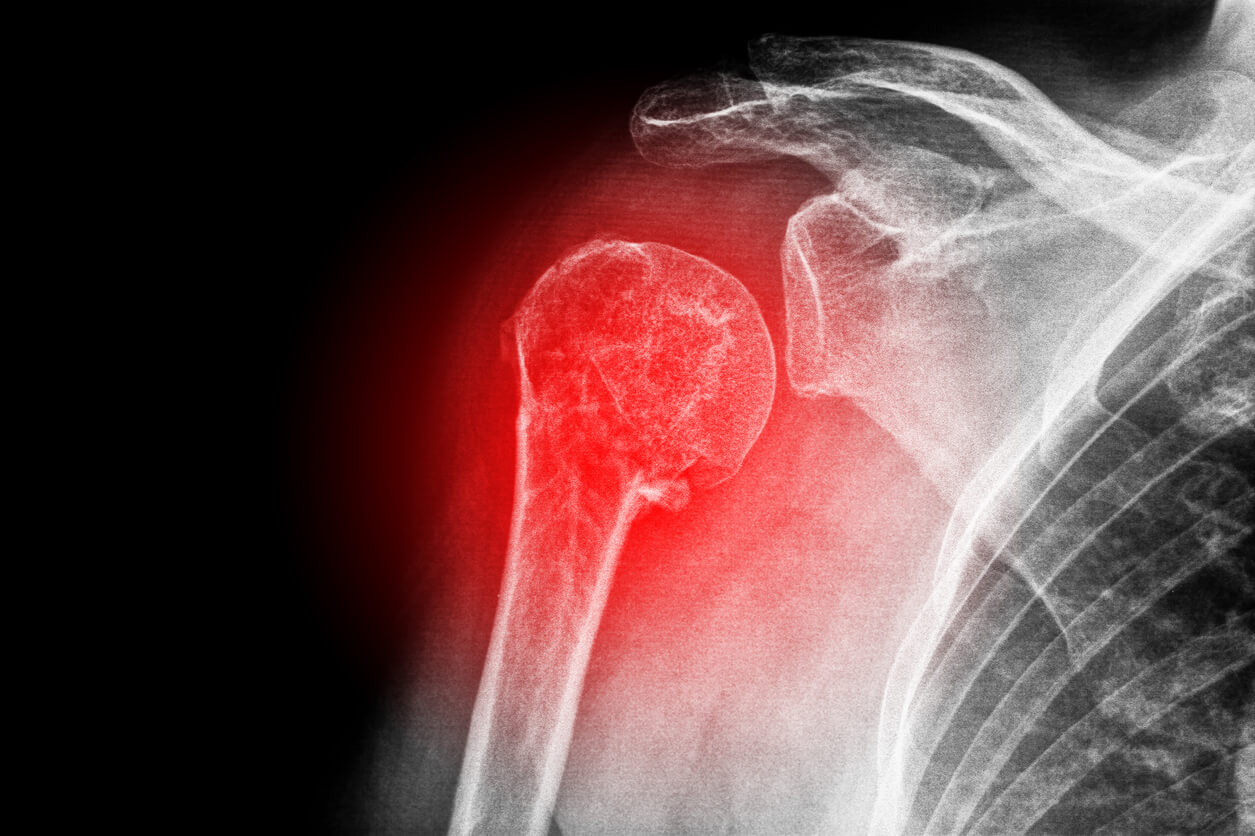

Can a Dislocated Shoulder Heal On Its Own? Dr. M. Tyrrell Burrus in TX Can A Dislocated Joint Heal On Its Own Unlike some other types of injuries, dislocated joints won't simply heal on. Picture of knee dislocations plus ligament and. Dislocations can happen to your shoulder, hip, knee, elbow, ankle, finger, thumb, or toe. If you suspect you have a dislocated joint,. Can a dislocated joint heal itself? When you dislocate your shoulder, a permanent change occurs where you stretch out. Can A Dislocated Joint Heal On Its Own.